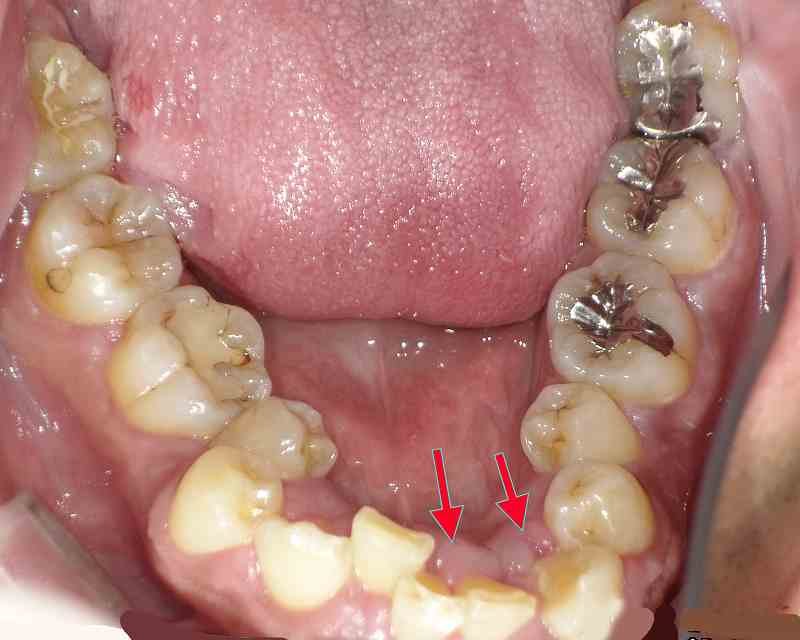

取り組み3:歯並びの改善

現代の子供たちは顎の成長が十分でなく、歯並びが悪くなることが多いです。当院では、「プレオルソ」というマウスピース型の装置を使った矯正治療を行っています。この装置は日中1時間と就寝時のみの装着で、口周りの筋肉を整え、歯並びを改善します。